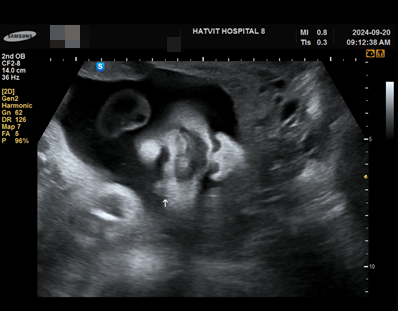

임신 30주 5일 햇빛병원 진료 백일해 가격 경산모 아기 크기 주차장 변경

안녕하세요! 또리기특맘입니다. 비가 와도 왜 안 시원하죠? 아침마다 환기시키는데 창문 열 때마다 아오 더...